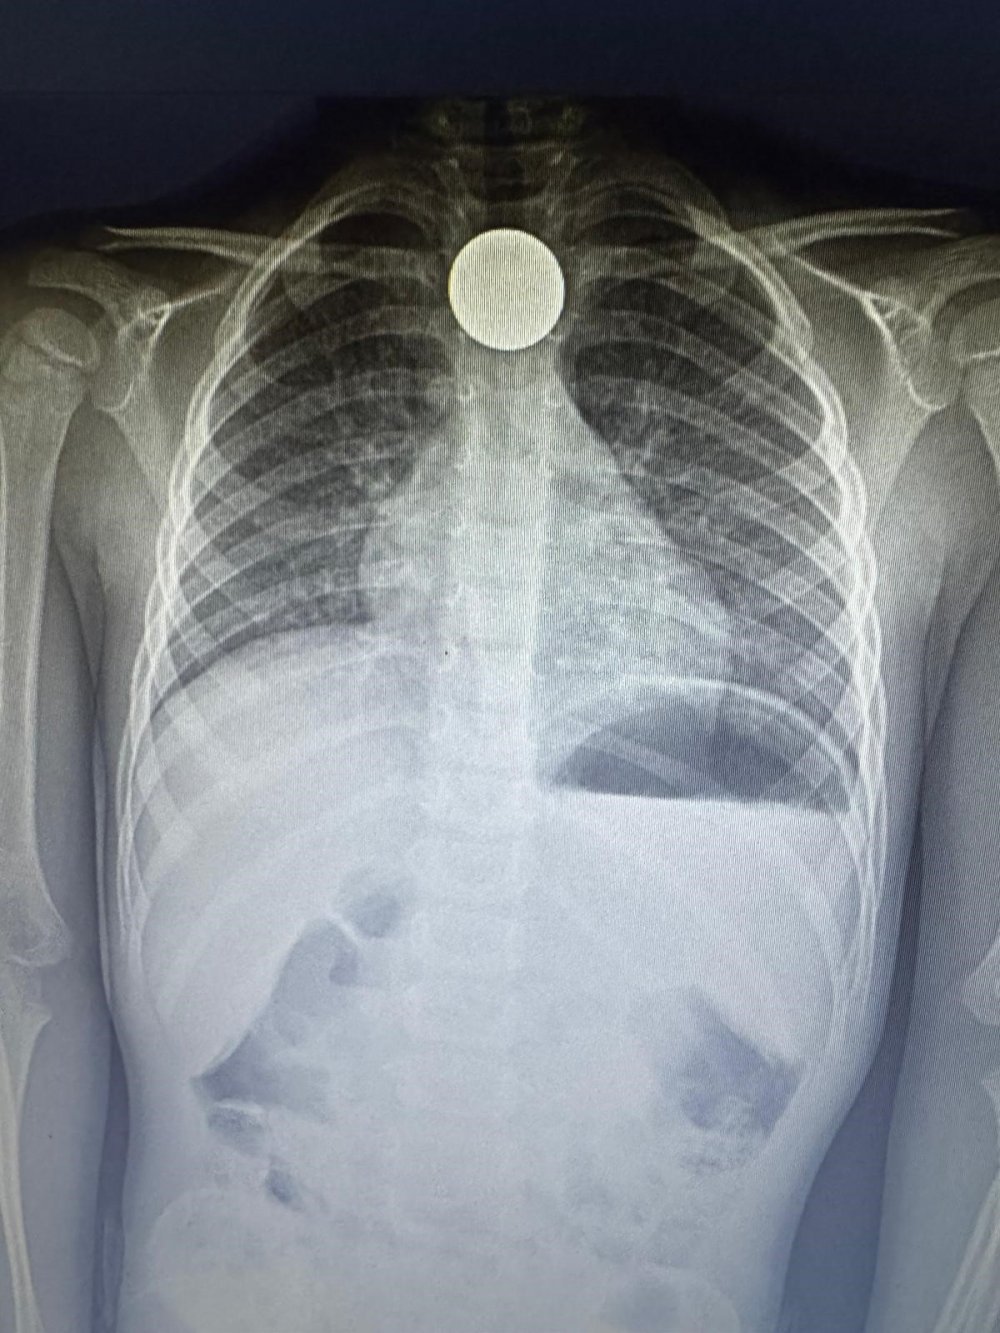

Çekilen röntgende paranın boğazda dik olarak kaldığı görüldü. Doktorlar, paranın yan yatması durumunda küçük çocuğun nefes almasına engel olabileceği ve nefessiz kalarak hayati risk oluşturabileceği aileye anlatıldı. Yapılan 4 saatlik operasyonun ardından para boğazdan çıkarılırken, küçük çocuk ertesi gün taburcu edildi.

Yaşadıklarını anlatan baba Ziya Özden Tezgel, ikizleri Aras Hasan ve Ali’yi okuldan aldıktan sonra eve geldiklerini belirterek, “Çocukları aldığımda Aras Hasan ve Ali’nin okulda Kızılay Haftası ile ilgili etkinlik yaptıklarını öğrendik. Kızılay’a bağış yapmak için biriktirdikleri paraların bulunduğu kumbaralarını getirdiler. Salonda hep birlikte paraları sayıyorduk. Anneleri yemek yaptığı için kısa süreliğine içeriye geçtik. Kısa süre sonra Ali yanımıza geldi. Hasan’ın para yuttuğunu söyledi. Anne çıkarmaya çalıştı ancak olmadı. Antalya Eğitim ve Araştırma Hastanesi’ne götürdük. Çekilen ultrasonda paranın boğazda takılı olduğu görüldü. Doktorlar ameliyata alacaklarını söylediler. Çünkü para Aras Hasan’ın boğazındaki dik duruyordu. İyi ki öyle durmuş, böylece nefes alıp vermesine engel değildi. Doktorlar paranın yan durması halinde çocuğumuzu kaybedebileceğimizi söylediler. 4 saat ameliyatta kaldı. Genelde bu yaştaki çocuklar durumu pek idrak edemiyorlar. Sonrasında ise para ölüme kadar götürebiliyor” dedi.